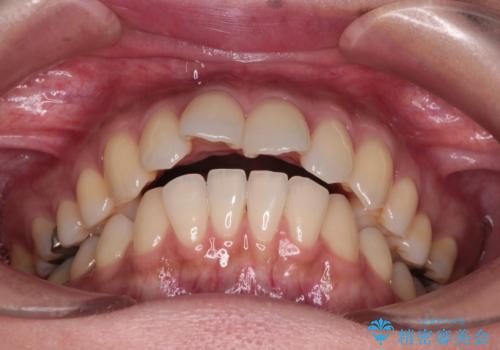

- 上の前歯の突出感を気にして来院された患者様です。

目立たない装置を希望とのことで、上顎左右第一小臼歯を抜歯し、インビザラインにて矯正治療を行うこととしました。